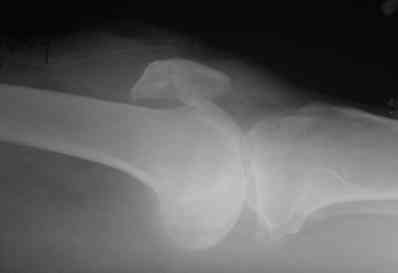

прилагаю снимки надколенника.

Где снимки надколенника?

Имеем дело с застарелым повреждением разгибательного аппарата и контрактурой коленного сустава. Согласен с д.Джолдасом - лечить как повреждение собственной связки надколенника. Учитывая сроки после травмы, возможно не получиться сопоставить костные фрагменты. Я бы рекомендовал сделать аутопластику собственной связки надколенника ( способ Лазишвили с соавт.)с блокированием проволочной петлей. Способ очень эффективен при многооскольчатых переломах надколенника,либо аллотендопластику собственной связки ( в ваших условиях можно использовать лавсановую ленту).После восстановления собственной связки возможно придется переместить головки квадрицепса либо произвести некоторые элементы миофасциотенотомии (Решается на операционном столе)

В приложении фото пациента с переломом надколенника 3 месячной давности. После мобилизации отломков, 4 главой мышцы бедра и полного разгибания голени оставался диастаз между костными фрагментами в 2 см. В связи с этим наложили модуль из аппарата Илизарова - 2 опоры и 2 спицы (в верхнем полюсе надколенника и верхней трети большеберцовой кости). Очень медленно (в течение 15 минут) путем накручивания гаек на стержнях растянули 4 главую мышцу бедра и устранили диастаз. Аппарат демонтировали и выполнили остеосинтез <стягивающей петлей>. Через 6 месяцев фиксаторы удалены. Автор данного <хирургического трюка> профессор из Австрии Vilmos Vecsei (<Гений ортопедии>, 2004, № 4, С. 94-95). Ваш случай не совсем идентичный по давности травмы и малой величине дистального отломка, но описанный <трюк> может оказаться полезным и при выполнении операции, которую рекомендует Джолдас.